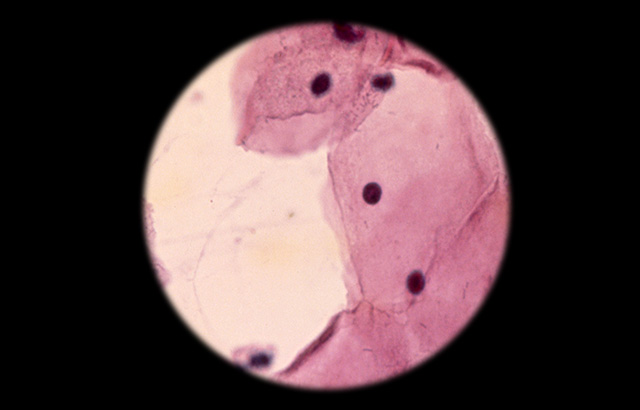

A cytologic smear under the microscope

To reduce the incidence of cervical cancer in developed countries, nationwide screening is offered to all women. Taking a small cluster of cells (‘cytology’) to diagnose disease before it progresses to cancer has been extremely effective. But in less developed countries, a lack of infrastructure and quality management have hampered widespread implementation of effective screening programmes.